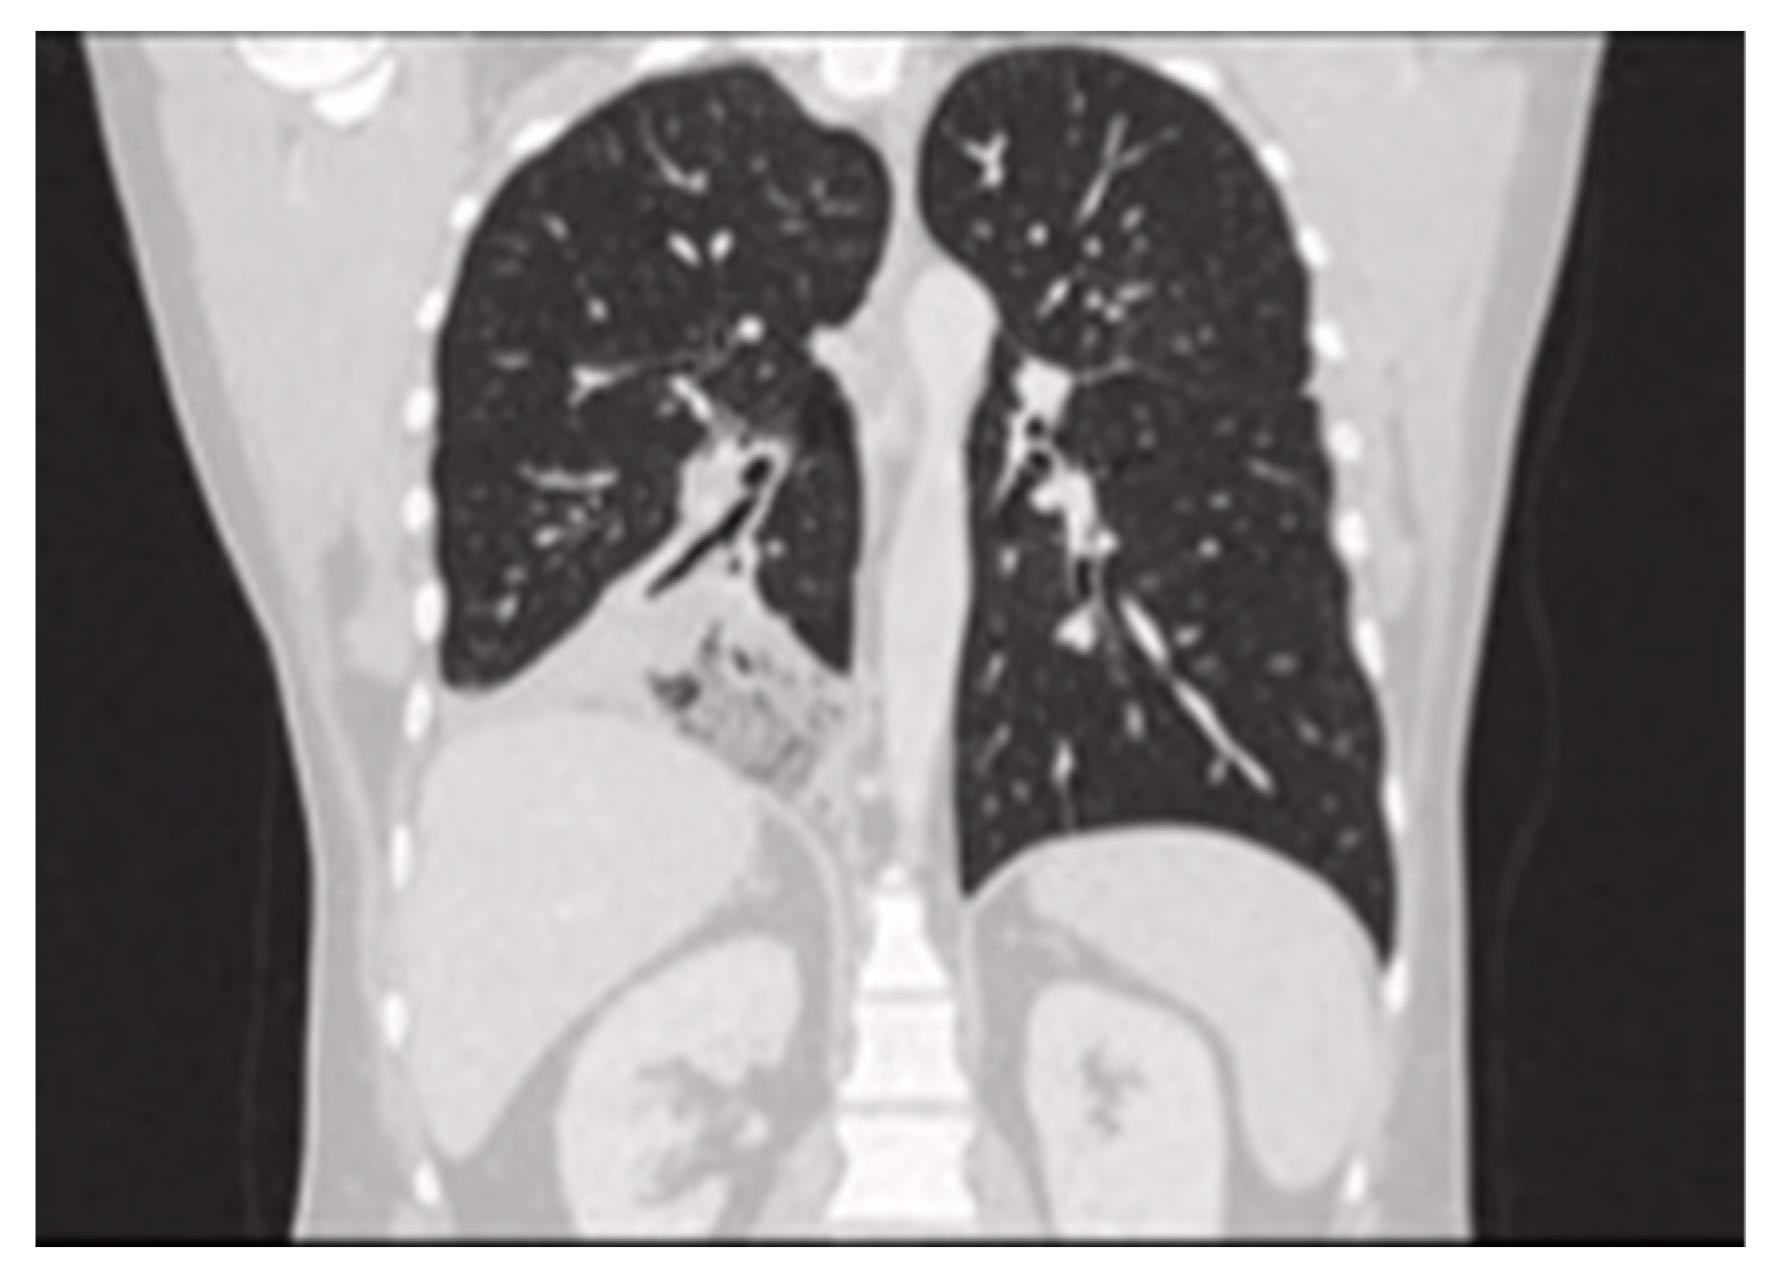

Pulmonary Sequestration (PS) represents the 0.15–6.45% of CPMs [3]; it is characterized by a mass of non-functioning lung tissue separated from the normal tracheobronchial tree and receiving vascular supply from a systemic artery (Figure 1). It is classified as Intra-lobar PS (IL-PS) when it is incorporated in the parenchyma of a lobe, and as Extra-lobar PS (EL-PS) when it is separated from the adjacent normal parenchyma by its own pleural envelope.

Figure 1. CT evidence of systemic arterial vascularization from descending thoracic aorta.